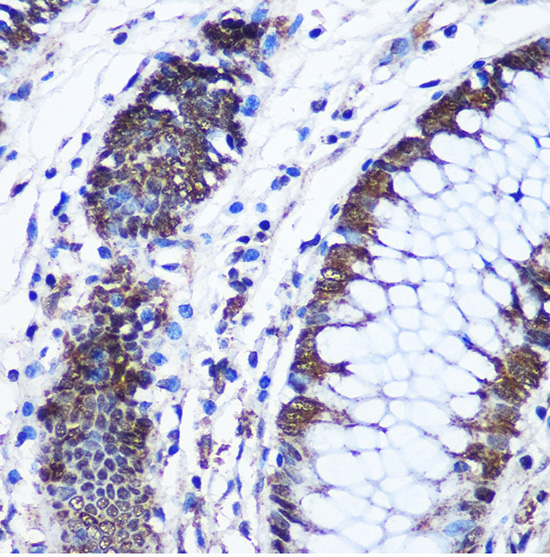

Immunohistochemistry of paraffin-embedded Human colon using CTCF Rabbit pAb.